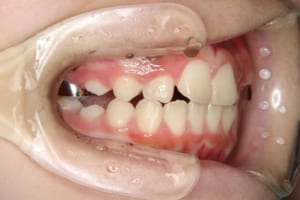

治療前

| 主訴 | 八重歯の生え方が気になる |

| その他/備考 | 上の犬歯が生えるためのスペースが全くない状態でした。放置すると重度の八重歯になることが想定されるケースです。 今回はあごの成長も利用しながら治療をするために、早めに後期治療(大人の矯正治療)に移行しました。 治療後レントゲン写真を見たところ、上顎前歯に若干の歯根吸収を認めました。 |